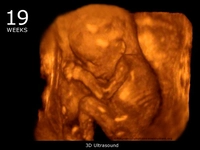

23 haftalık gebelik, hamileliğin ikinci trimesterinin sonlarına yaklaşıldığı bir dönemi ifade eder. Bu süre zarfında, hem anne hem de bebek için birçok önemli gelişim ve değişiklik yaşanmaktadır. Bu makalede, 23 haftalık gebelik dönemindeki fiziksel ve duygusal değişimlerin yanı sıra, bebeğin gelişimi, anne adayının sağlığı ve dikkat edilmesi gereken hususlar ele alınacaktır. Bebeğin Gelişimi23 haftalık gebelikte bebek, hızla büyümeye devam etmekte ve birçok önemli gelişim sürecinden geçmektedir. Bu dönemde, bebeğin gelişimiyle ilgili bazı önemli noktalar şunlardır: